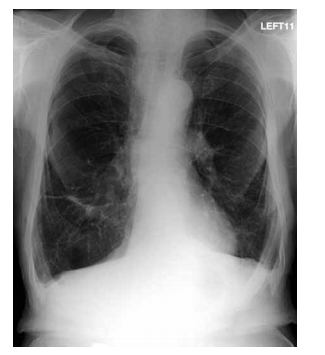

Mulher, 68 anos, sem antecedentes mórbidos, apresenta dor torácica ventilatório-dependente, de forte intensidade com piora à inspiração profunda e dispneia intensa. Recebeu alta há 15 dias após internação para cirurgia de correção de fratura de colo de fêmur. Exame físico: bom estado geral, taquipneica leve, afebril, PA = 120x70 mmHg, saturação periférica de oxigênio = 89% em ar ambiente, ausculta cardíaca normal e ausculta pulmonar com estertores crepitantes finos em bases. Realizados eletrocardiograma e tomografia computadorizada de tórax com contraste, ilustrados a seguir.

Mulher, 68 anos, sem antecedentes mórbidos, apresenta dor torácica ventilatório-dependente, de forte intensidade com piora à inspiração profunda e dispneia intensa. Recebeu alta há 15 dias após internação para cirurgia de correção de fratura de colo de fêmur. Exame físico: bom estado geral, taquipneica leve, afebril, PA = 120x70 mmHg, saturação periférica de oxigênio = 89% em ar ambiente, ausculta cardíaca normal e ausculta pulmonar com estertores crepitantes finos em bases. Realizados eletrocardiograma e tomografia computadorizada de tórax com contraste, ilustrados a seguir.

Mulher, 68 anos, sem antecedentes mórbidos, apresenta dor torácica ventilatório-dependente, de forte intensidade com piora à inspiração profunda e dispneia intensa. Recebeu alta há 15 dias após internação para cirurgia de correção de fratura de colo de fêmur. Exame físico: bom estado geral, taquipneica leve, afebril, PA = 120x70 mmHg, saturação periférica de oxigênio = 89% em ar ambiente, ausculta cardíaca normal e ausculta pulmonar com estertores crepitantes finos em bases. Realizados eletrocardiograma e tomografia computadorizada de tórax com contraste, ilustrados a seguir.